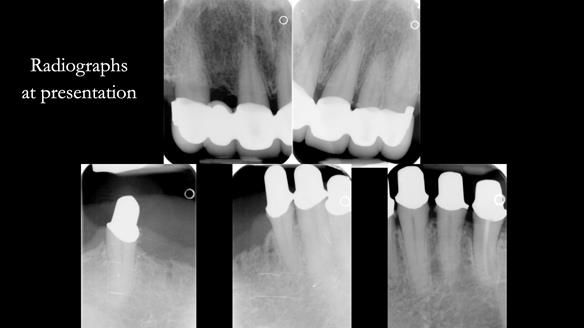

Replacement lower overdenture & upper RPD for Jackie

This Newsletter show Jackie’s case from start to finish – a technically demanding case involving replacing a telescopic crown-supported lower overdenture and an upper precision attachment-retained partial denture.

The real challenge was the lack of space for the lower overdenture.